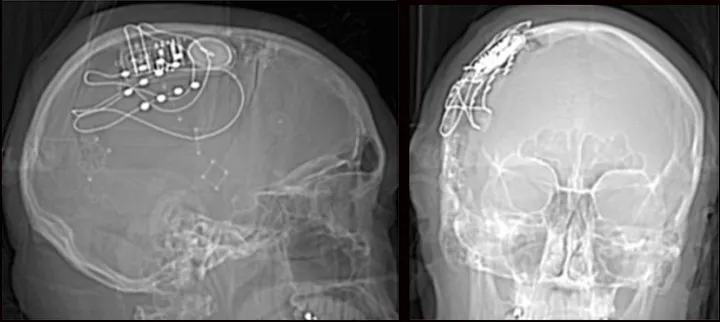

植入位置的选择是脑机接口的一个重要方面,需要仔细考虑技术和医学因素。这里有几个地方可以植入脑机接口,这取决于癌症的阶段,肿瘤的类型等。

皮质内深度电极:这是一种薄型多电极阵列,可植入大脑以记录深层结构的神经活动。它们可用于癌症位于大脑深部的病例。

皮质内深度电极

硬膜下电极:这些电极放置在大脑表面,通常在头骨下方,但在硬脑膜(覆盖大脑的保护膜)上方。它们可以提供高分辨率的神经活动记录。

植入硬膜下电极

硬膜外电极:这些电极放置在硬脑膜的外表面,提供来自大脑最外层的记录。

这张图片显示了每个电极的不同位置: